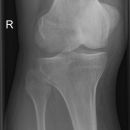

Knie a.-p (1. Ebene)

Fraktur, Luxation, entzündliche und degenerative Veränderungen

Kniegelenkspalt muss frei abgebildet sein, Tibiaplateau lateral muss strichförmig dargestellt werden, medial leicht oval, Kniescheibe mittelständig.